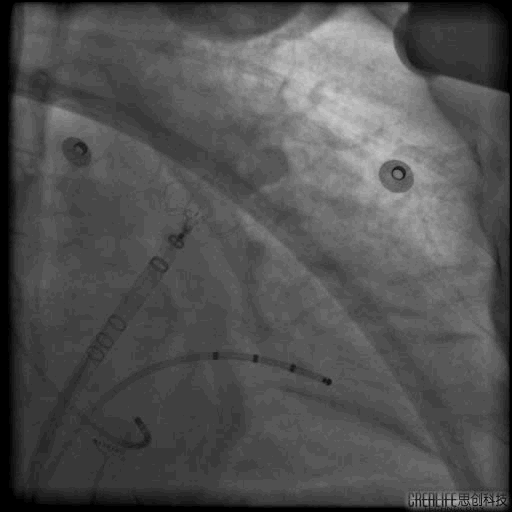

1.房间隔穿刺

房间隔穿刺TEE

RAO30° CAU25°造影,左心耳形态充分暴露,可以观察到心耳属于反鸡翅形状。内部梳状肌较发达,深度较浅。

DSA测量开口17mm,深度19mm,与CT测量结果类似,考虑选择24mm watchman封堵器,首选X3轴向进行封堵。

4. 封堵操作

术中在猪尾导管的保护下,逆时针旋转输送鞘,尽量将输送鞘送入上叶。稳定输送系统,体外预借1mm深度,送入封堵伞,逆时针旋转稳定输送鞘,术中缓慢释放封堵伞。

走上叶缓慢展开后即刻造影观察,无残余分流。压缩比测量12.5%~21%。牵拉测试稳定,符合PASS原则,可以释放。